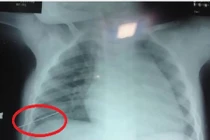

Cứu sống bé trai 3 tuổi bị kim đâm xuyên lồng ngực

(Kiến Thức) - Một bé trai 3 tuổi bị kim đâm xuyên lồng ngực gây thủng phổi. Rất may cháu đã được phẫu thuật kịp thời.

Thông tin từ Bệnh viện Hữu nghị Việt Nam - Cu Ba Đồng Hới, Quảng Bình cho biết, phía bệnh viện đang tích cực điều trị cho cháu T.C.S.C (nam, 3 tuổi, trú ở xã Hoàn Trạch, Bố Trạch, Quảng Bình) do kim khâu đâm thấu vào lồng ngực khiến phổi của cháu bị thủng.

Cháu C. được người nhà đưa đến Bệnh viện Hữu nghị Việt Nam - Cu Ba Đồng Hới, Quảng Bình vào chiều ngày 1/5, trong tình trạng đau tức ở vùng ngực và khó thở. Ngay sau khi tiếp nhận cháu C., các y bác sĩ đã làm xét nghiệm... và chẩn đoán cháu bị dị vật nhọn đâm xuyên lồng ngực phải gây thủng phổi.